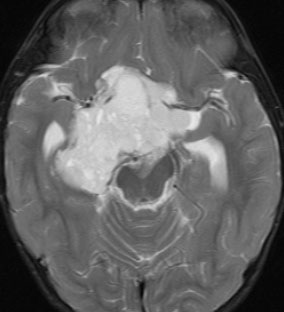

幼児の視路の毛様粘液性星細胞腫です。T2強調画像(左側)で白く高信号に写るのが特徴です。ガドリニウム増強ではまだらになっていますが,均一に真っ白に高信号になることも多いです。乳幼児のものは,ドロドロに柔らかい腫瘍です。

whole optic pathway pilocytic astrocytomaとは

両側の眼窩内視神経から視交叉、視索,外側膝状体,内包後脚,視放線近位部までが腫瘍化しています。FLAIRで高信号で,不規則にガドリニウム増強されます。これを手術摘出したり生検したりしても無駄です。放射線治療は不可能であり治療方法は化学療法のみです。

この子はCDDP/VCRの化学療法から開始して12年になりますが,今は無治療でわずかな視力ですが学校に通っています。優等生です。自然退縮を見ていますが,今後も変化する可能性はすこし残しています。